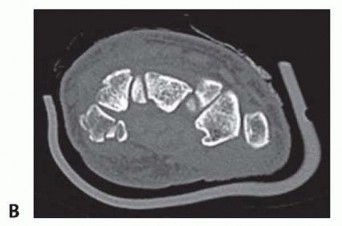

Despite optimal plain radiography, advanced imaging is frequently required. High-resolution computed tomography (CT) scanning with fine axial, coronal, and sagittal reconstructions has become the gold standard and the imaging modality of choice for complex carpal trauma. CT scans definitively confirm occult fractures, delineate intra-articular comminution, and reveal subtle associated injuries missed on plain films. They allow the surgeon to mentally construct a 3D model of the fracture, facilitating precise preoperative templating of screw trajectories and implant sizes. If dynamic instability is suspected but unconfirmed, an Examination Under Anesthesia (EUA) combined with real-time fluoroscopy (utilizing stress and distraction views) is performed immediately prior to the definitive procedure to finalize the surgical blueprint.

Clinical & Radiographic Imaging Archive